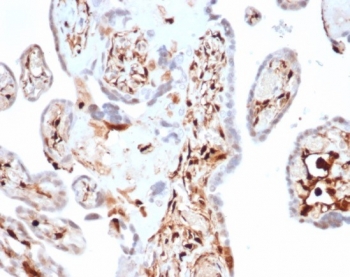

IHC staining of FFPE human spleen tissue with S100A4 antibody (clone S100A4/7097). HIER: boil tissue sections in pH 9 10mM Tris with 1mM EDTA for 20 min and allow to cool before testing.